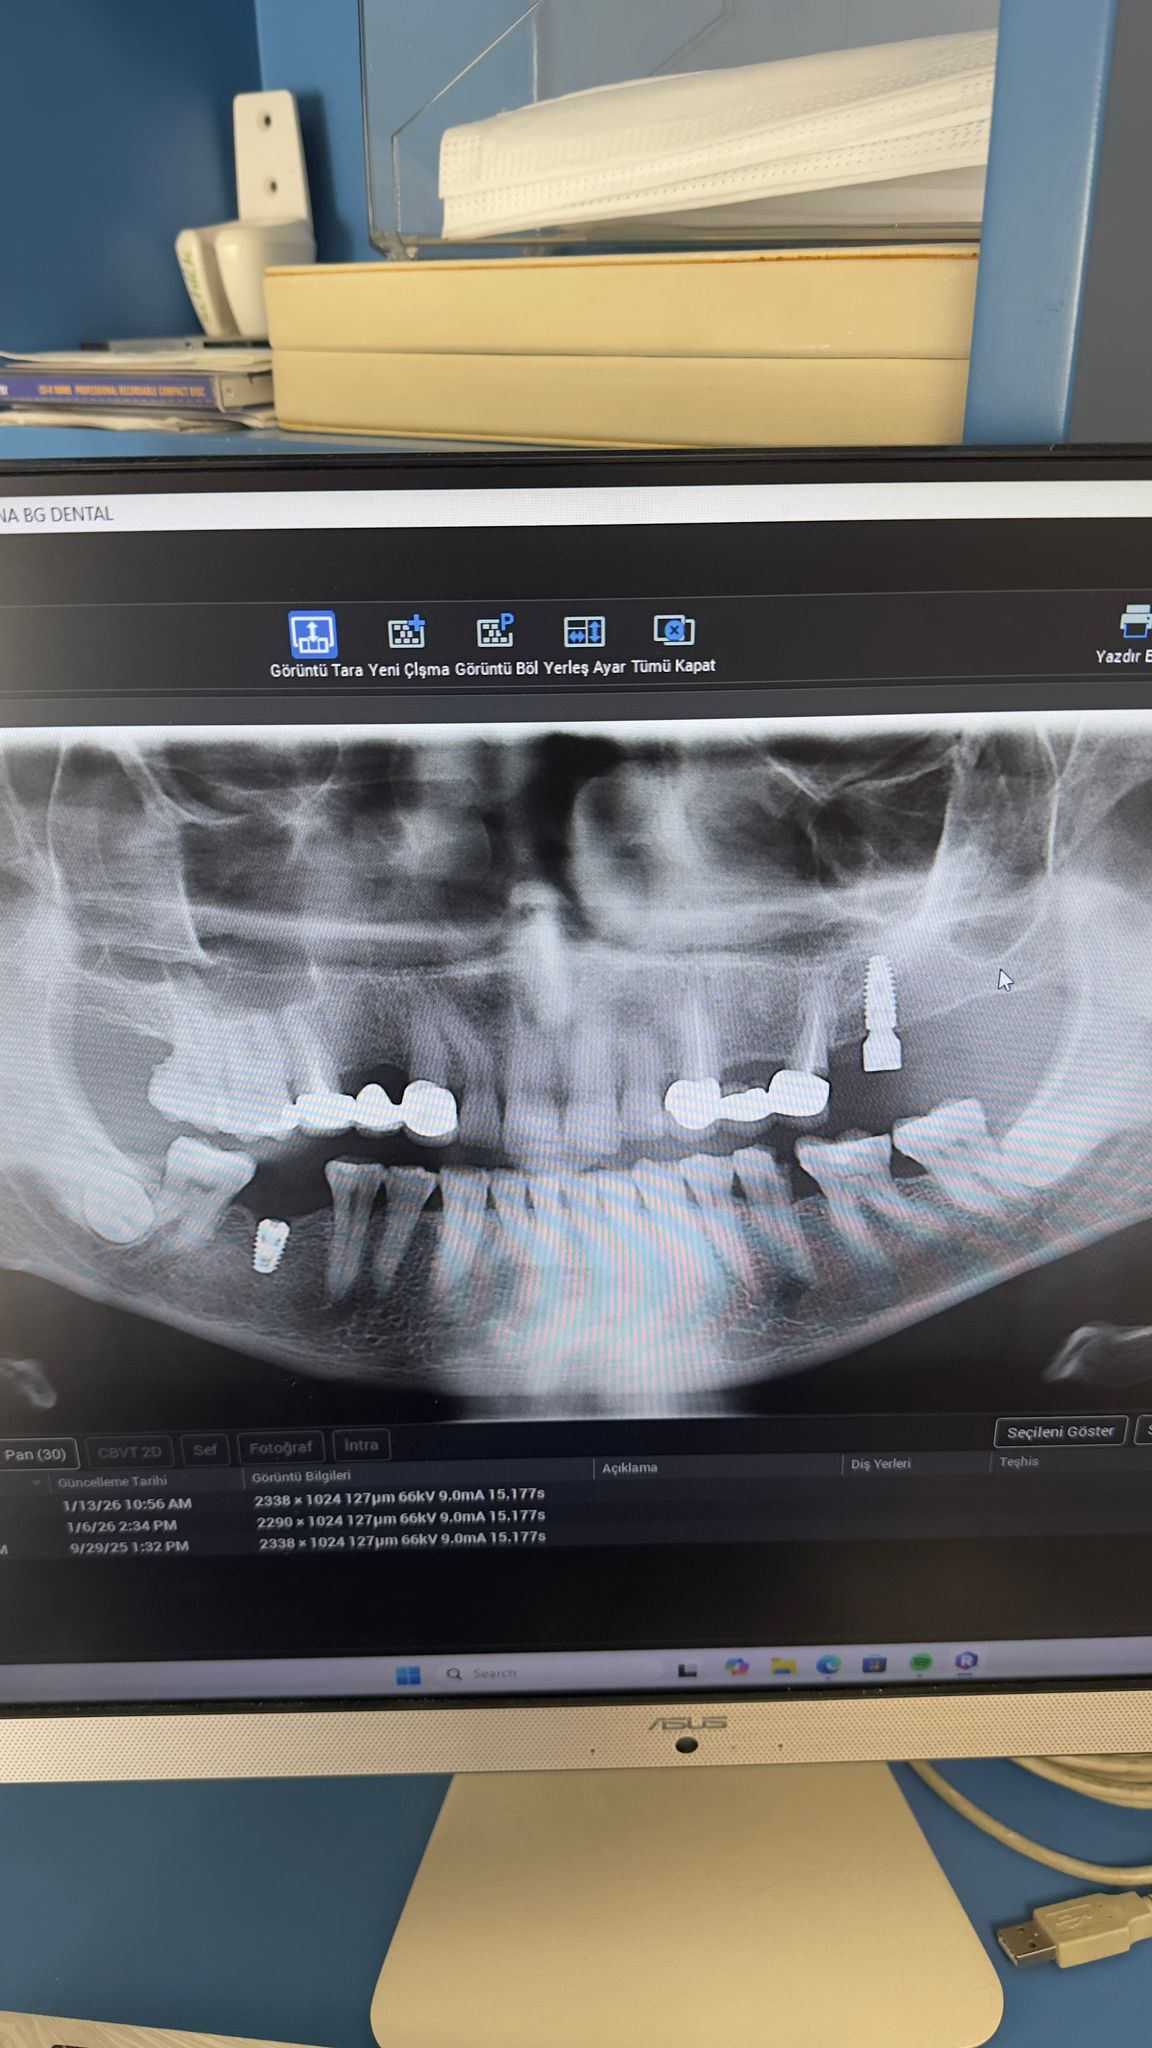

Ahmet Doğan ( 15.10.1972)

Hastanın sağ üst ve alt 1. büyük azı dişlerinin eksik olduğu tespit edilmiştir. Gerekli muayene ve tetkikler yapıldıktan sonra sağ üste 3.7 mm, sağ alta 4 mm çapında iki implant yerleştirilmiştir. Osteointegrasyon için beklenmektedir. 29 Eylül muayene 13 Ocak implantlar yerleştirildi.